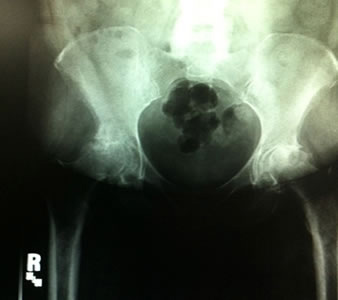

Dr. Testerman's cas is a forty-five year old female, morbidly obese with bilateral hip disease. She is currently household ambulatory and otherwise confined to a wheel chair, although able to independently transfer herself to and from bed. X-rays show destructive bilateral OA of the hip with such severity it is hard to determine if the underlying disease is hip dysplasia or not. The right hip head has collapsed making true measurement of femoral offset difficult.

Due to her relative young age, body weight and the likely fact that she will be facing one or more revisions in her lifetime Dr. Testerman decided a more bone conservative tissue sparing approach would be in her best interest. Although her body weight certainly did not lend itself to a conservative soft tissue approach this device does not require resection into the greater trochanteric and abductor musculature area.

At 5' 2" and 250 lbs this was going to be a challenge for any approach, devise, and surgeon. In addition this was being done at a new hospital with a new team that had not seen this devise before. Prior to surgery, John and I had a chance to review the x-rays and we did not see anything that should hinder the selection of the ARCTM Stem. We did have a conventional stem on backup and always recommend that a conventional stem be available. I did suggest that he take an intraoperative x-ray once the trials were implanted.